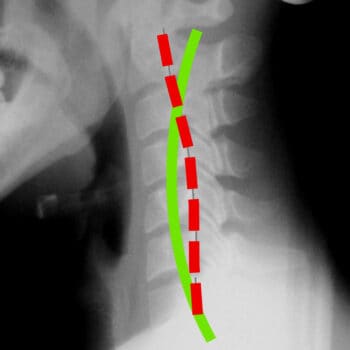

BEFORE

AFTER

Spinal Alignment

Correct posture is at the core of the Chiropractic BioPhysics® method of treatment. The curves in your spine act as levers, shock absorbers, and resistance to gravity; they also protect and reduce forces acting on the spinal cord and nerve tissues. But, gravity, age, poor posture, improper physical activity, injury, and disease can all play a role in the misalignment of your spinal curves and, as a result, your entire body.

Following a scientific analysis of your posture and the curvature of your spine through x-ray and postural analysis software, a treatment plan is developed. Based on your deficits, spinal condition, and other findings, appropriate treatment will be prescribed to restore proper alignment, relieve pain, and improve function.